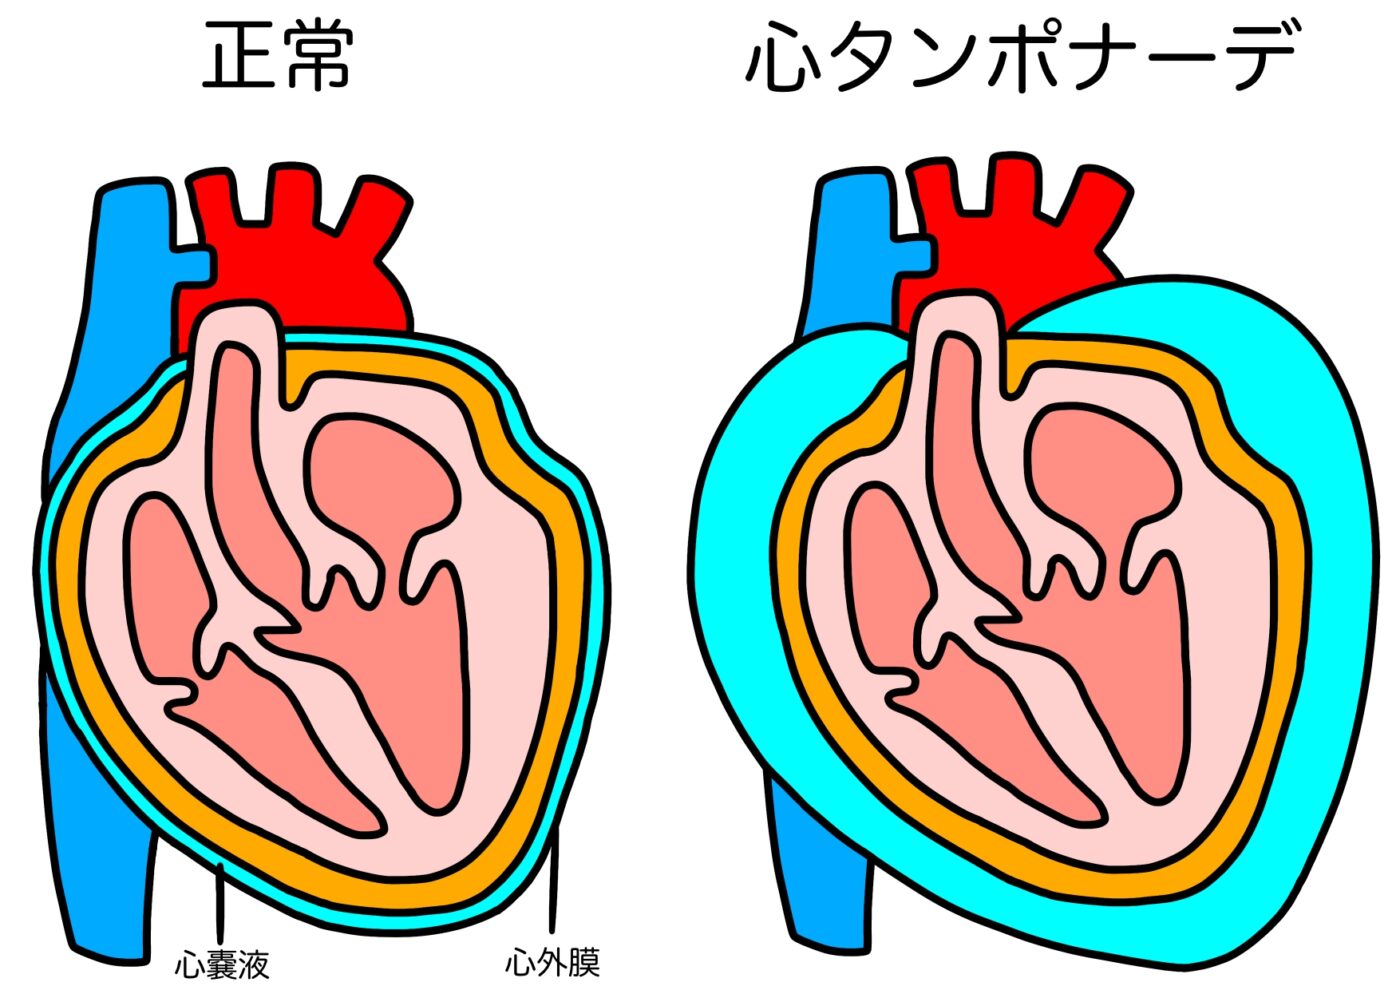

心臓は心膜と呼ばれる膜で覆われています。

この心膜と心臓の隙間に何らかの原因で血液や水が貯まり、心臓が圧迫され動きが悪くなる状態を”心タンポナーデ”と呼びます。

そして貯留している液体を心嚢水と呼びます。